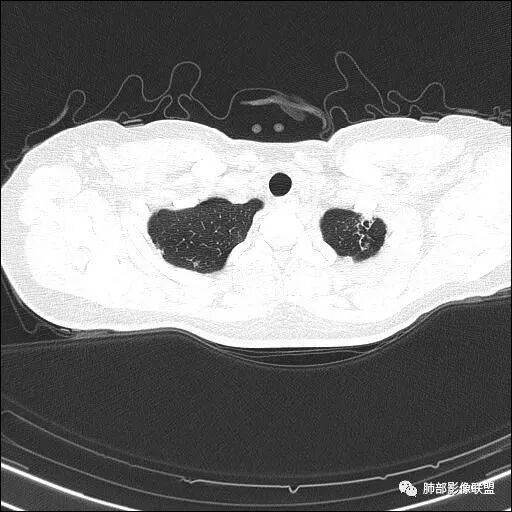

【每日晨读】双肺上叶多发薄壁空洞

1.年轻女性,体检发现肺部病灶

血常规正常

2.双肺多发薄壁空洞影、条索影及结节影,边界较清楚,密度偏高不柔和,散乱,但有成簇倾向或堆积感,胸膜下分布为主,双肺上叶分布为主。

3.空洞相当不规则,缺乏张力,未见血管穿行,未见壁结节,未见液平。

4.双肺门及纵隔未见肿大淋巴结。未见胸腔积液。